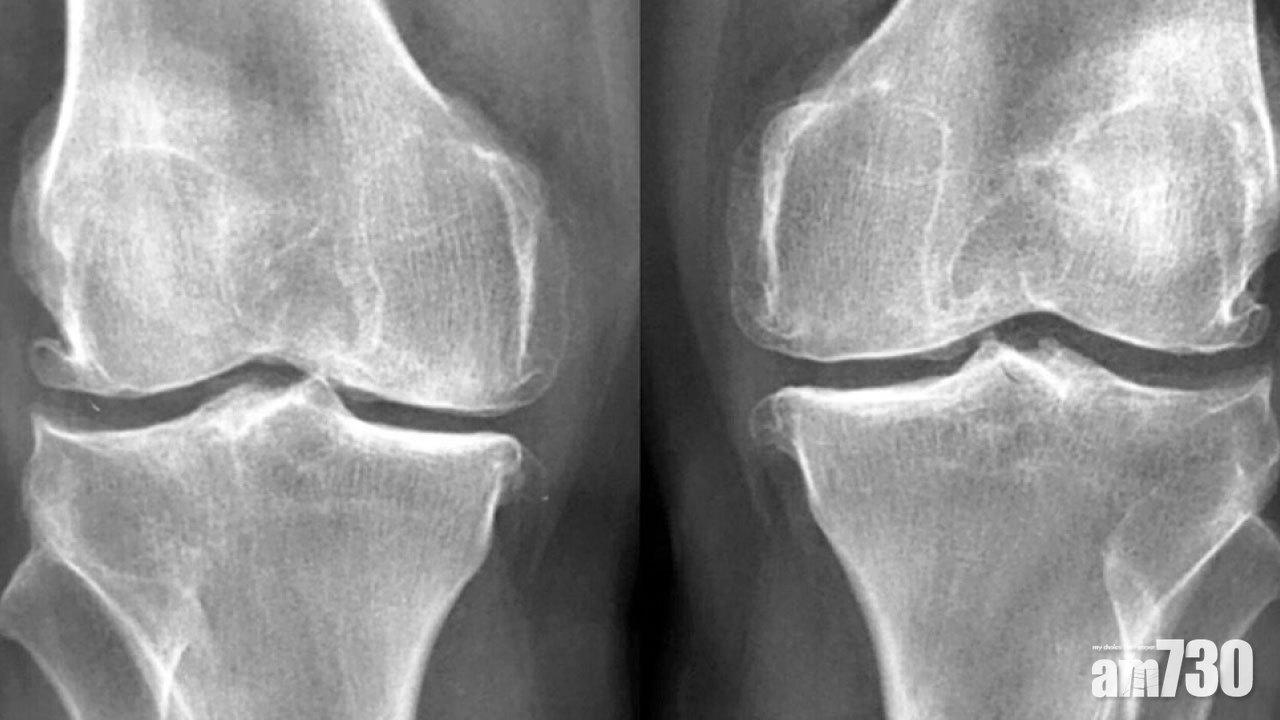

其實造成收成期(50歲後)患上膝痛的原因,與軟骨磨蝕有莫大關連。當膝關節表面的軟骨日漸耗損,硬骨便會互相摩擦,除了帶來痛楚外,更會形成骨刺並引致膝關節變形。但到底是誰,多年來破壞軟骨和摧毀關節?答案正是「年輕人」:年輕時的你!

對於年輕時曾健於射波的你,運動的確可強身健體。但過量的膝關節活動與碰撞,例如跑樓梯和跳躍動作,卻可促使軟骨耗損。一旦發生意外創傷,更可造成前十字韌帶或半月板撕裂。若不及時診治或接受手術,亦會令膝關節變得不穩定而加速軟骨磨蝕,結果膝關節在收成期前便提早退化。

對於年輕時曾辛勞工作的你,工作時久蹲或長跪,都會令髕骨軟骨受損,長遠會導致髕股關節退化。至於從事文職而久坐的你,股四頭肌會因減少使用而變得無力,容易患上髕股關節綜合症:患者在上落樓梯或蹲下時,會感到前膝痠痛。加上人到中年而體重上升,亦會加重雙膝關節的負擔。